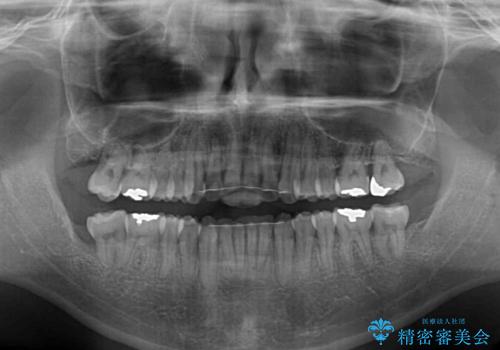

最終的にはゴムかけなどを活用して改善することができましたが、4年近い治療期間を要することとなりました。

デコボコは抜歯をすることなく解消できる程度であったため、インビザラインにより矯正治療を行うこととしました。

インビザラインは1日22時間を目標にマウスピースを装着することで歯列を改善するものです。